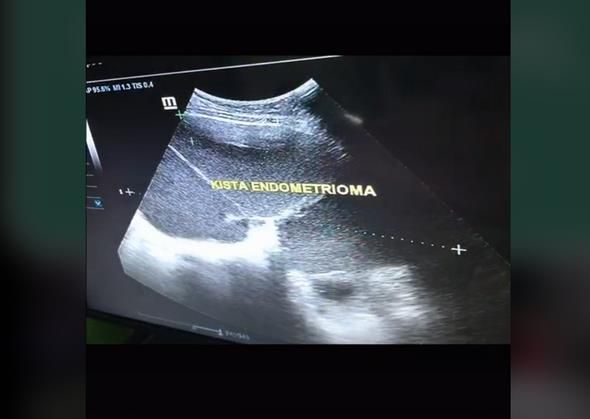

Namun, sesudah menjalani pemeriksaan USG, ternyata bukan gambar janin yang dilihat melalui layar monitor.

Apa yang disangka janin berusia 9 bulan rupa-rupanya adalah tiga kista berukuran besar sedang tumbuh di dalam rahimnya!